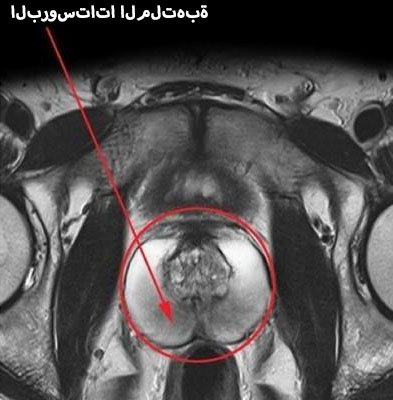

البروستاتا الطبيعية والملتهبة

تصوير البروستاتا بالأشعة السينية